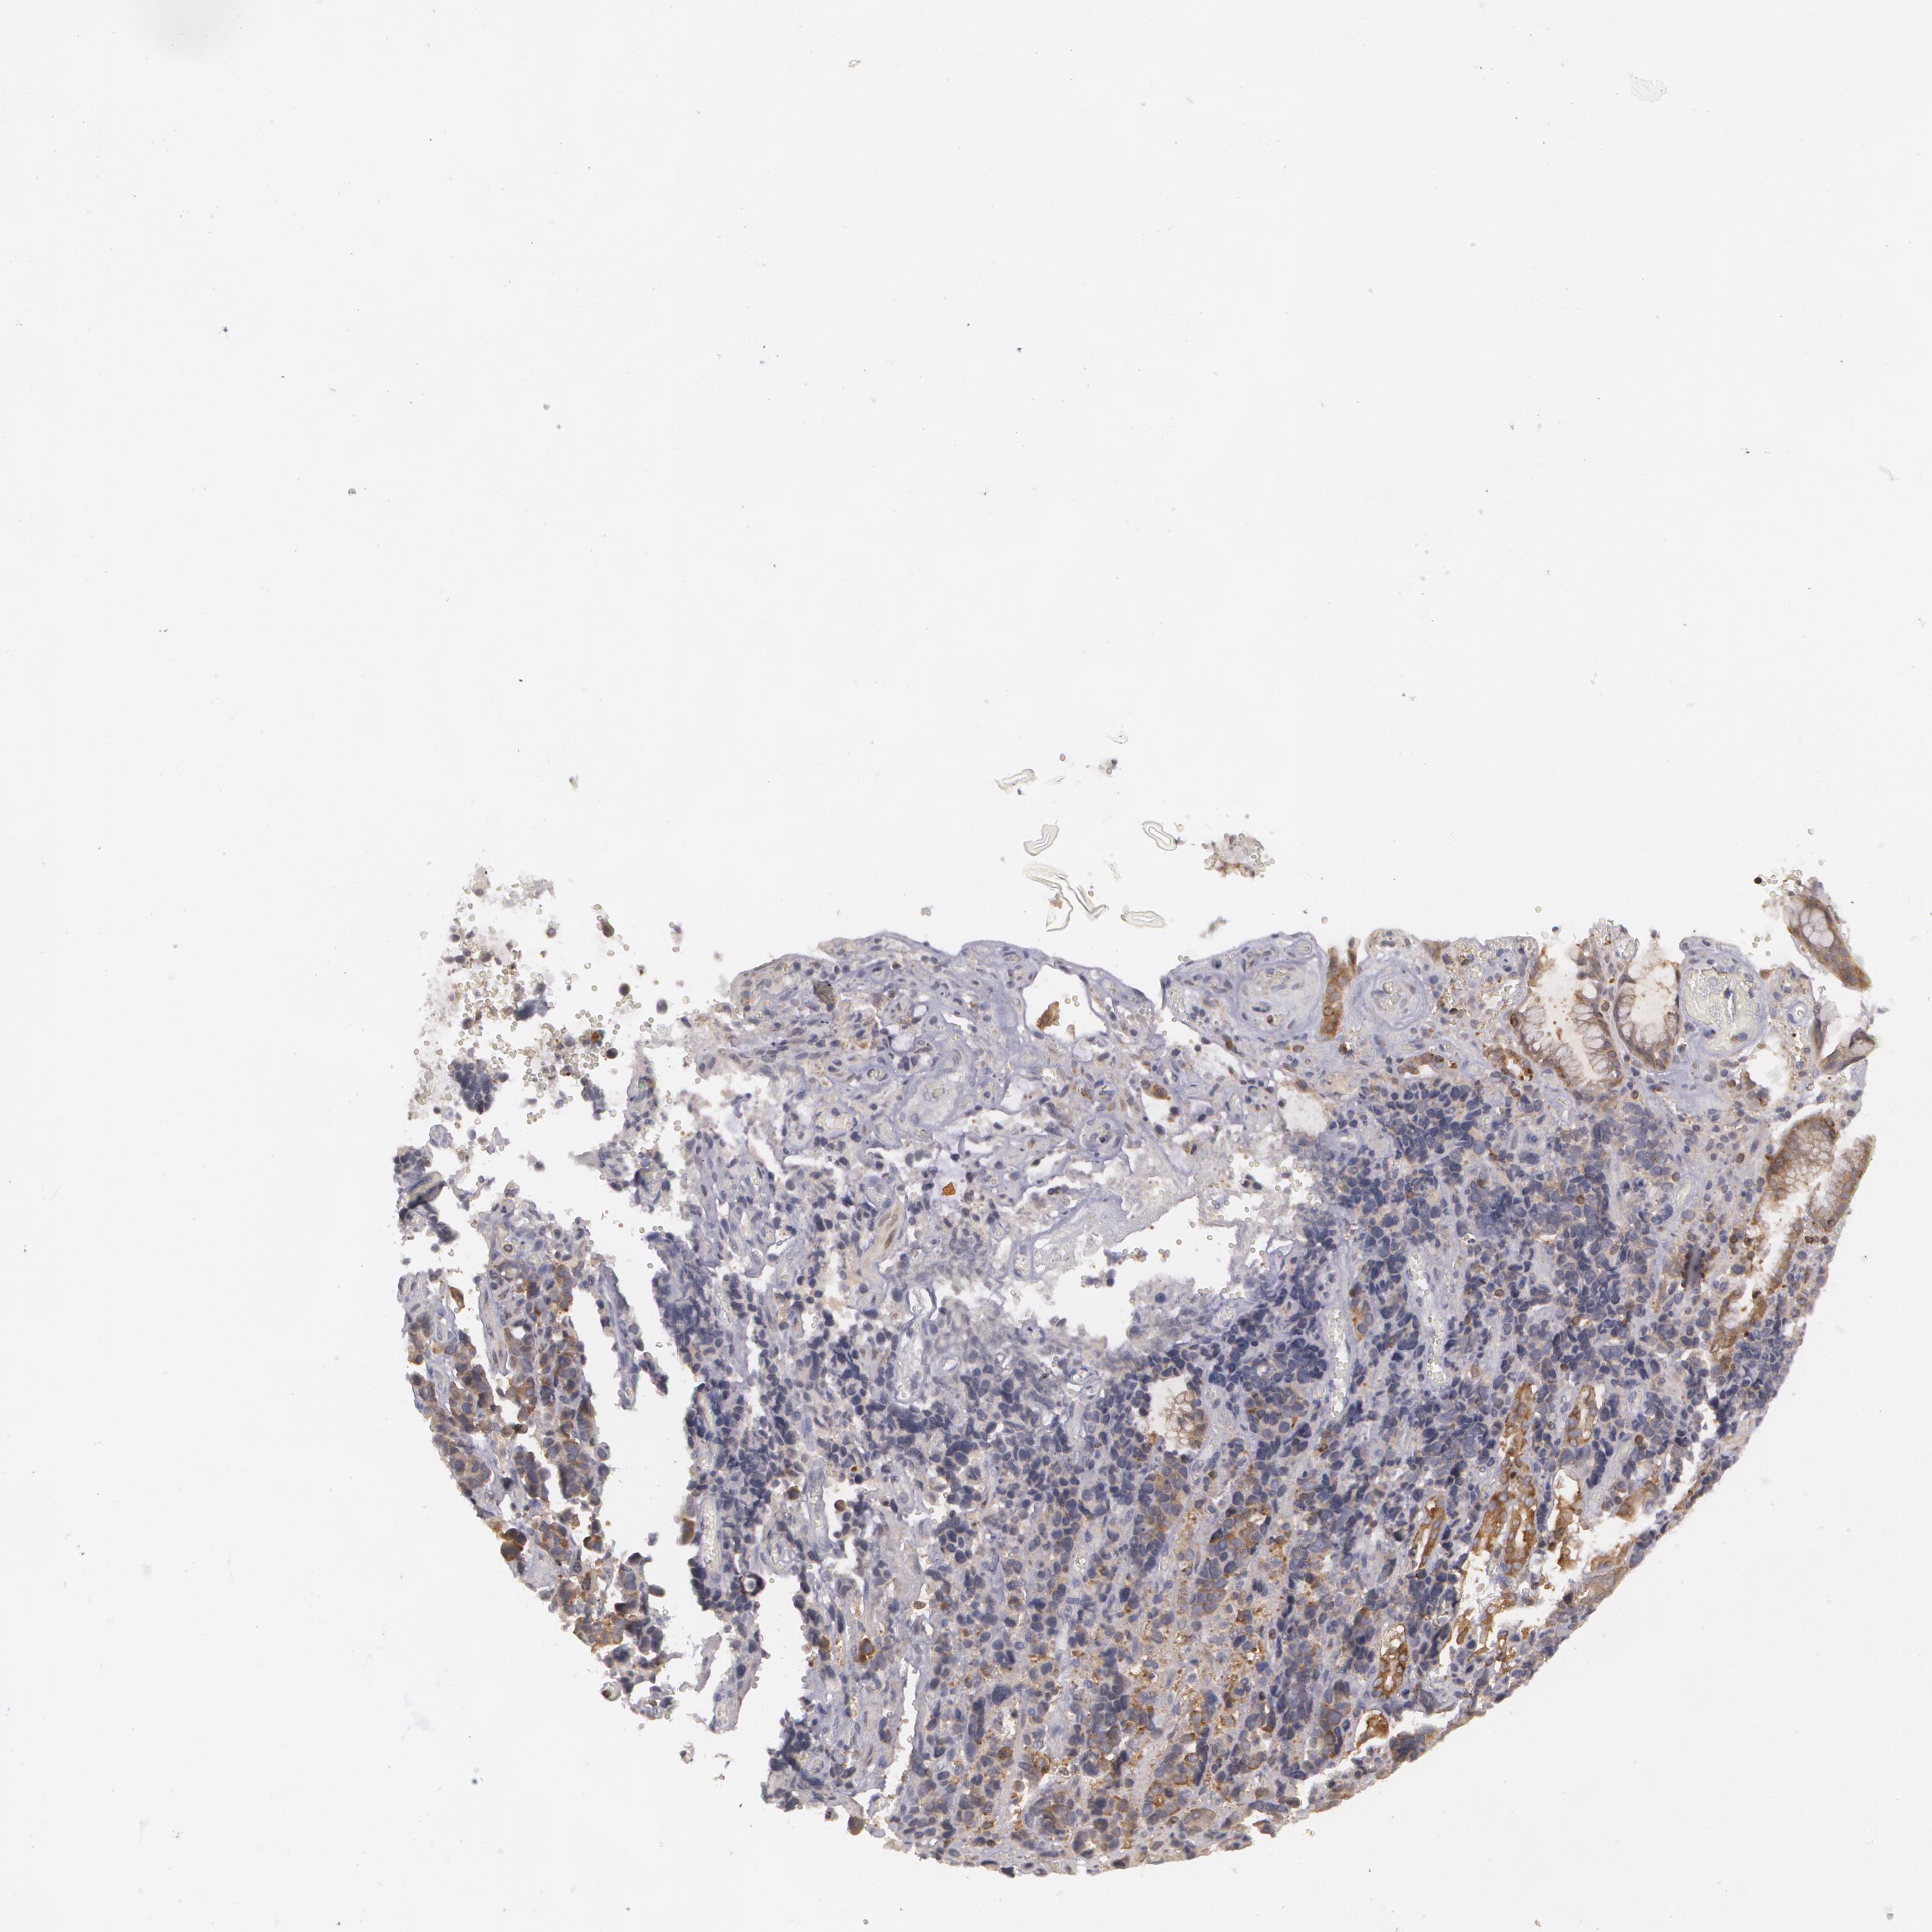

STOMACH CANCER - Protein expressioni

A mouse-over function shows sample information and annotation data. Click on an image to view it in a full screen mode. Samples can be filtered based on level of antibody staining by selecting one or several of the following categories: high, medium, low and not detected. The assay and annotation is described here.

Note that samples used for immunohistochemistry by the Human Protein Atlas do not correspond to samples in the TCGA dataset.

Antibody stainingi

Antibody staining in the annotated cell types in the current human tissue is reported as not detected, low, medium, or high, based on conventional immunohistochemistry profiling in selected tissues. This score is based on the combination of the staining intensity and fraction of stained cells.

Each image is clickable and will lead to virtual microscopy that enables deeper exploration of all samples and also displays staining intensity scores, fraction scores and subcellular localization as well as patient and tissue information for each sample.

Antibody HPA003894

Antibody HPA005437

Antibody CAB001945

Staining

High

Medium

Low

Not detected

Adenocarcinoma, NOS

Adenocarcinoma, High grade